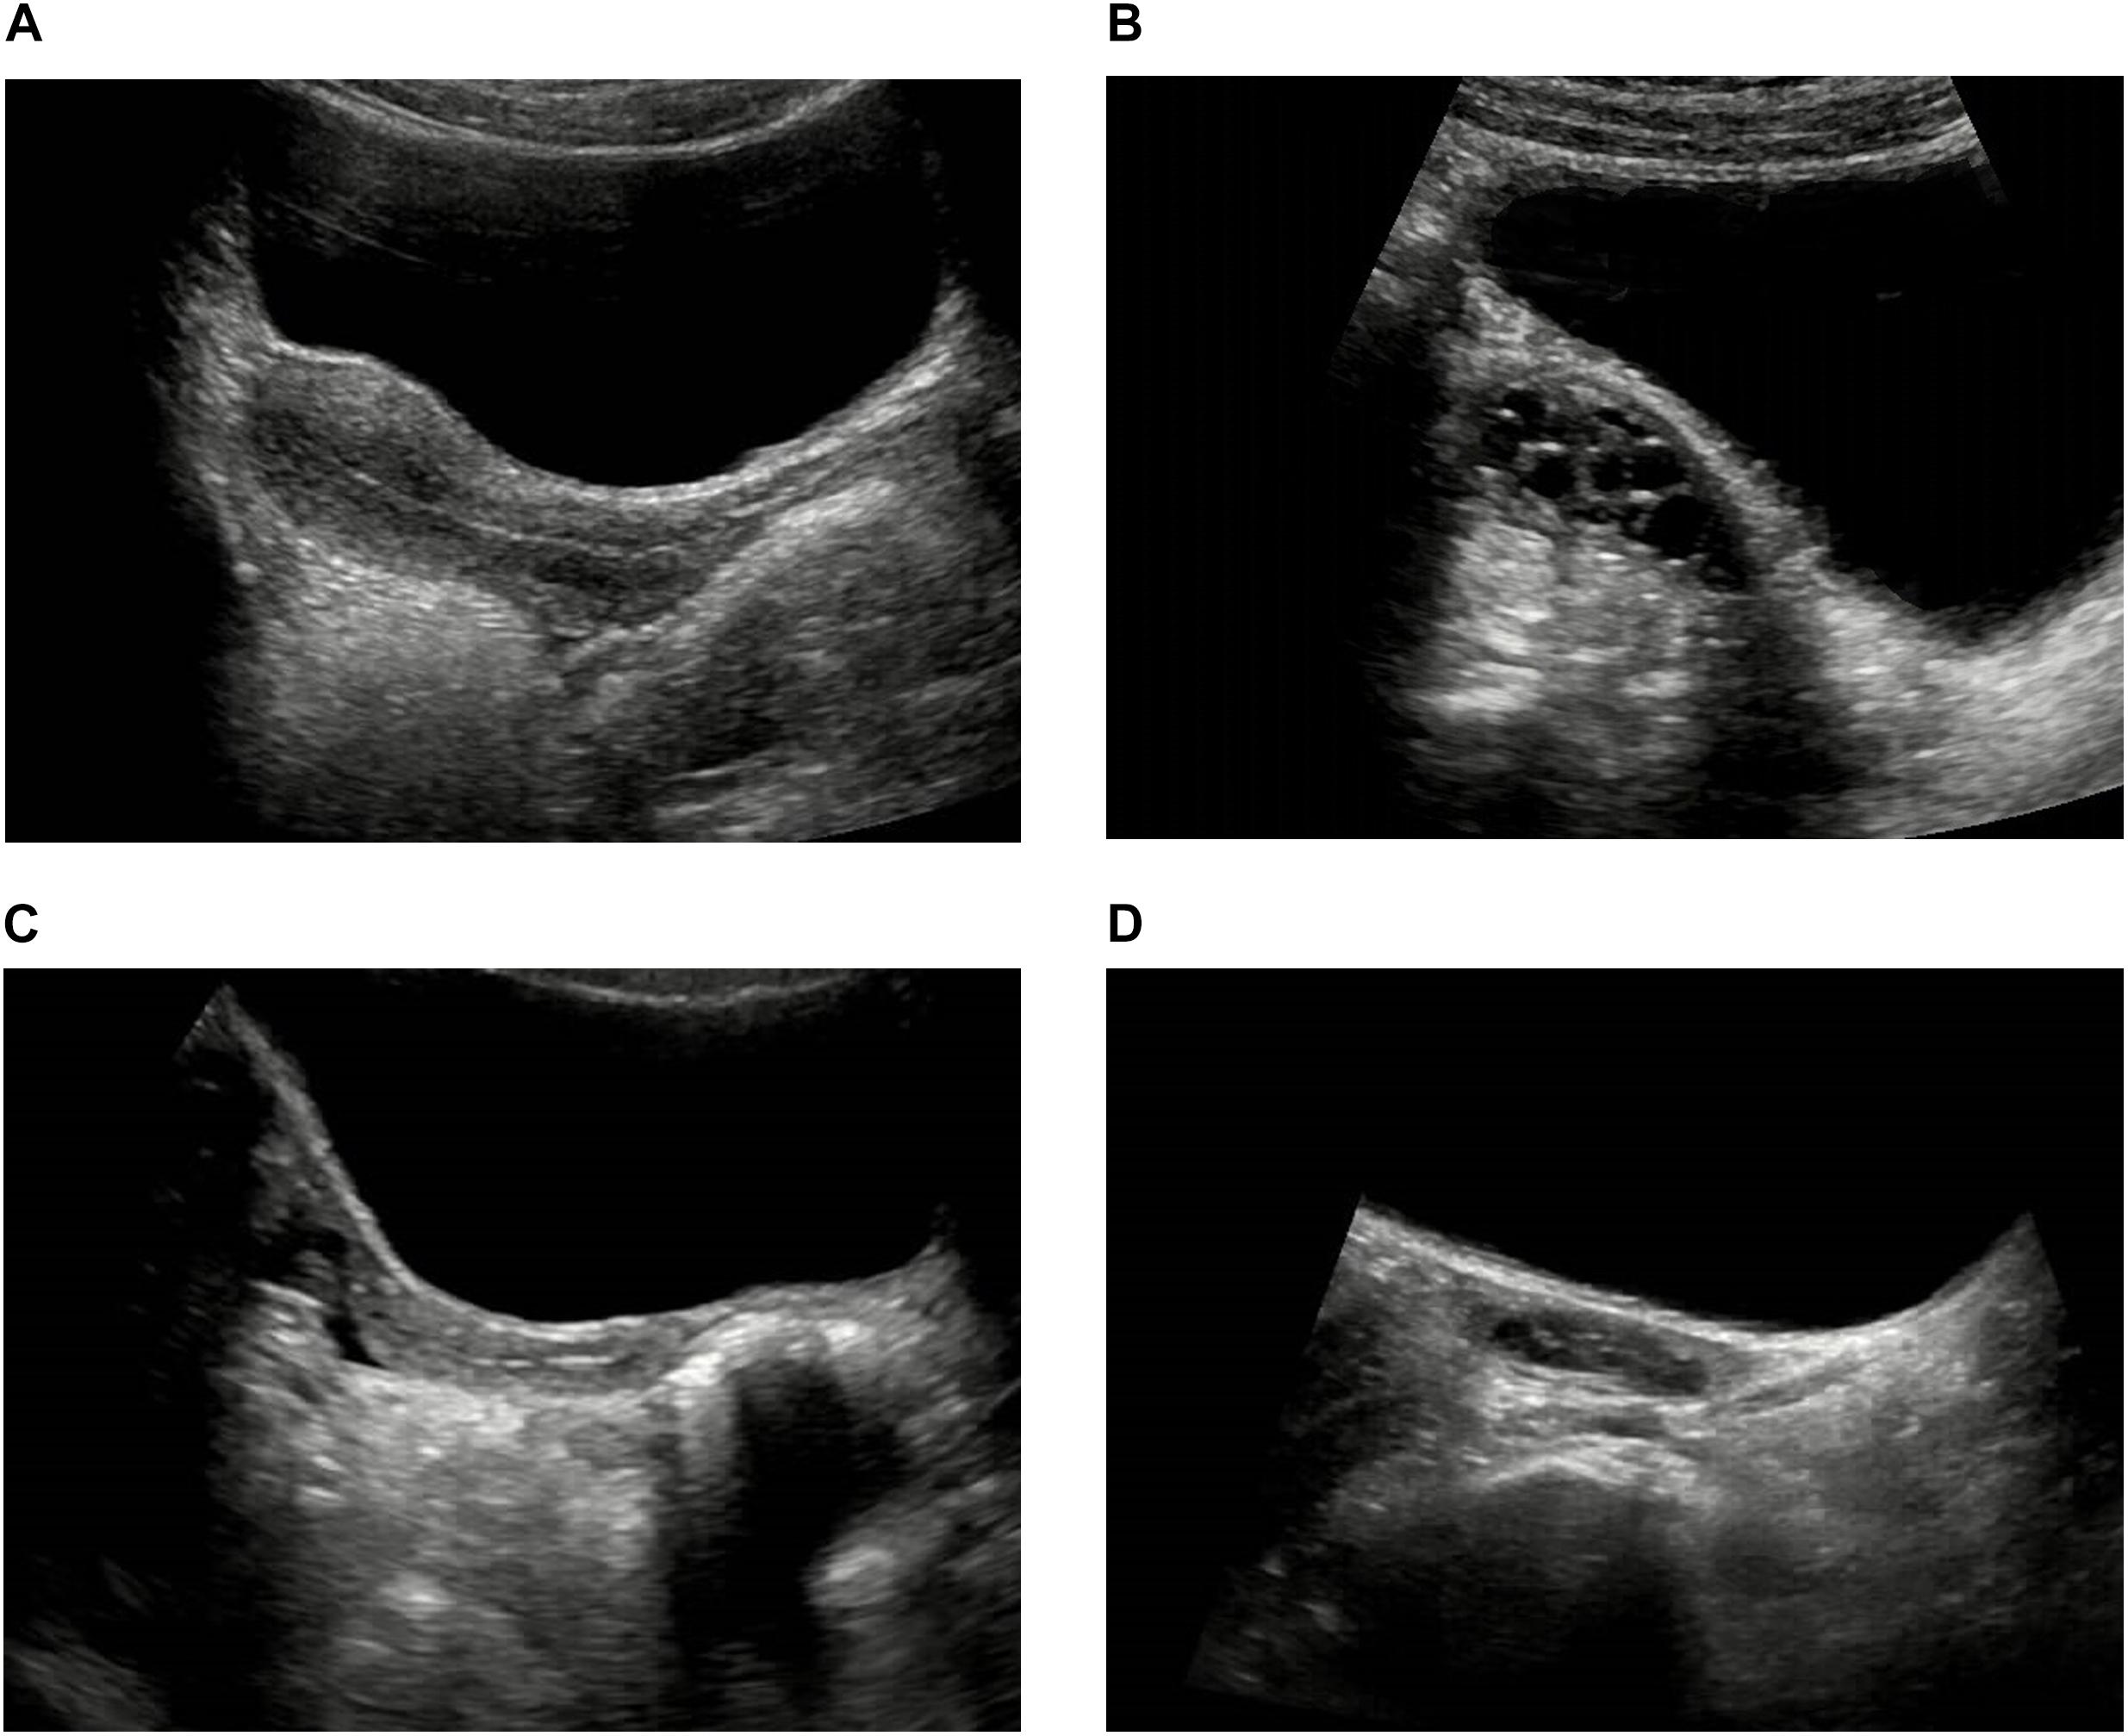

Ultrasonido Pélvico Ginecológico Dr. Emmanuel Acuña

Source: dremmanuelradiologo.mx